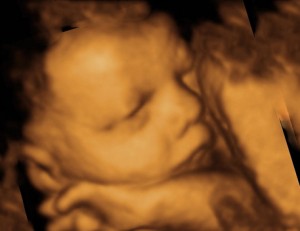

Диагностика развития патологии плода

УЗИ плода

Если предыдущий анализ на патологию плода позволяет выявить генные отклонения, то УЗИ позволяет исключить врожденные патологии. Однако проводить его можно только при условии, что специалист опытный именно в вопросах пренатальной диагностики ВПР, а также с 20 недели после зачатия. Не рекомендуется экономить, обращаясь в более дешевые диагностические центры. Вполне вероятно, они использую устаревшее оборудование, с которым выявить патологию невозможно.

На первом скрининге, который обычно проводится на сроке 11-14 недель беременности, можно выявить такие патологии, как хромосомные аномалии (например, синдром Дауна), а также некоторые анатомические дефекты плода, такие как пороки развития сердца и нейралгические аномалии. Скрининг включает в себя ультразвуковое исследование и анализ крови на биохимические маркеры, что позволяет оценить риск наличия этих патологий.

Регулярно проходите ультразвуковое исследование. Это один из самых эффективных способов раннего выявления патологий развития плода. УЗИ позволяет врачам оценить состояние плода и выявить возможные аномалии на ранних сроках беременности.